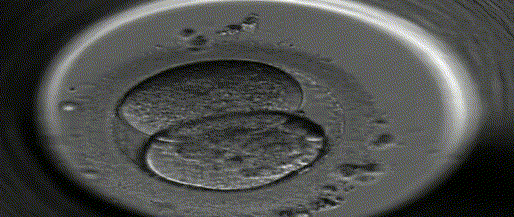

受精卵开始进行有丝分裂的同时,在输卵管内借着输卵管蠕动和纤毛推动,向子宫腔方向移动,约在受精后第3~4日,分裂成由16个细胞组成的实心细胞团,称桑椹胚,继续发育成为囊胚。

约在受精后第4~5日早期囊胚进入子宫腔并继续发育成晚期囊胚

约在受精后第6~7日,晚期囊胚侵入子宫内膜,称为胚泡着床